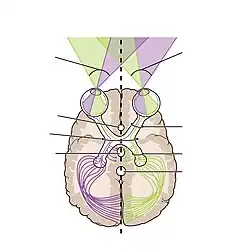

El recorrido "ojo-lóbulo occipital"

Cabe mencionar que la información transmitida desde los ojos al lóbulo occipital es reorganizada, ya que, desde que se entrecruzan (formando el quiasma óptico) se intercambia parte de las fibras de cada nervio óptico hacia el lado opuesto a través de las cintillas ópticas (los nervios del ojo izquierdo y del ojo derecho se separan en 2 conjuntos de fibras, dejando a las fibras que le pertenecen al campo visual izquierdo de cada ojo sean convergidas, igualmente a las que pertenecen al lado derecho). Lo cual permite que la información del campo visual tenga un registro más exacto al momento de llegar a los ganglios geniculados (en donde se reclasifican las fibras). Desde estos salen las radiaciones ópticas (haz amplio de fibras nerviosas, una izquierda y una derecha) los cuales atraviesan a cada hemisferio hasta llegar al lóbulo occipital.